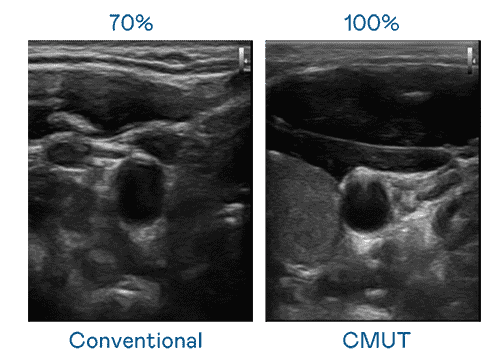

CMUT 技术是一种用电容式微机电元件来产生超音波讯号的技术。。。与传统 PZT 压电式技术相比,,,CMUT 频宽增加 30%,,更宽频的超音波讯号让影像解析度大幅提升,,,,是实现高影像品质医疗超音波扫描、、、、促进精准医疗发展的关键技术。。。

大频宽带来超清晰影像

超音波影像的解析度高低,,,首先取决于探头能发出的讯号频宽。。彩神vll CMUT 可提供高清晰的超音波讯号,,,提供高频宽、、、、高灵敏度、、、、影像纹理细节更高的超音波影像,,,,协助医护人员缩短影像判读时间及利用精准的医疗影像进行诊断。。。。